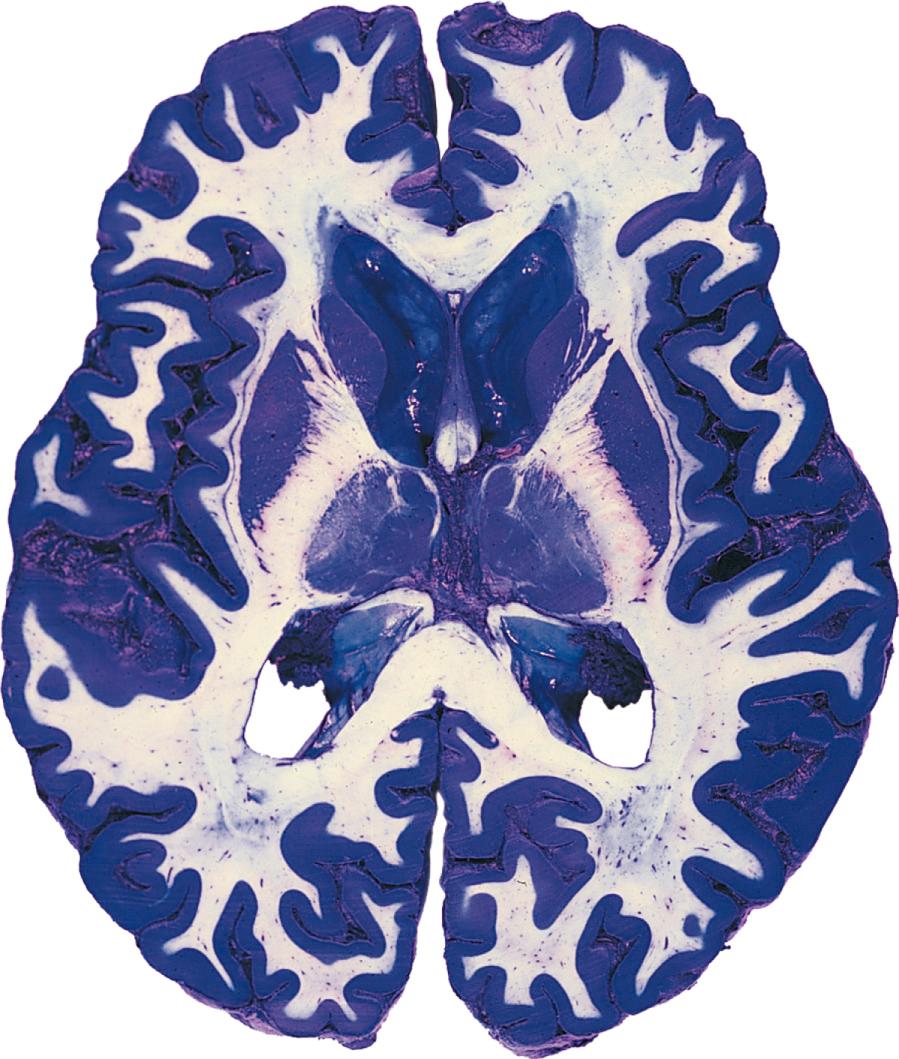

For the most part, the CNS is easily divisible into gray matter and white matter ( Fig. 1.9 ). Gray matter refers to areas where there is a preponderance of cell bodies and dendrites. (In life, however, gray matter is actually a pinkish-gray color because of its abundant blood supply.) White matter refers to areas where there is a preponderance of axons; many axons have a myelin sheath (described later in this chapter) that is mostly lipid and therefore has a fatty, white appearance.

Fig. 1.9, Axial (horizontal) slice of a whole human forebrain, approximately 6-mm thick, stained by a method that differentiates between gray and white matter. Pretreatment with phenol makes the white matter resistant to the blue copper sulfate stain, so white matter appears white and gray matter appears bright blue.